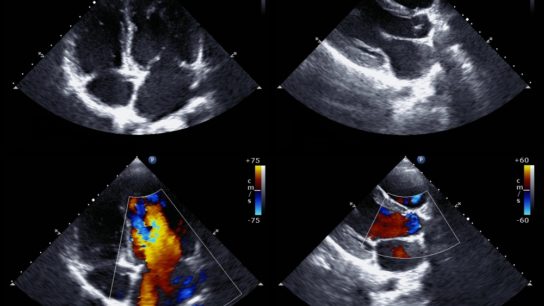

Spinal cord stimulation (SCS) with a closed-loop system that uses recorded evoked compound action potentials (ECAPs) is superior to a fixed-output, open-loop system for patients with chronic back and leg pain.